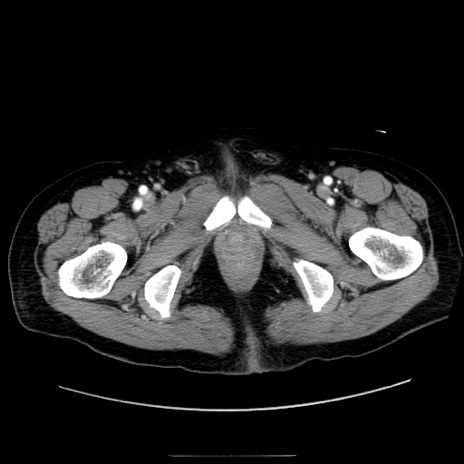

症例30(横断像)

【症例】80歳代男性

【主訴】臍周囲痛

【現病歴】約6時間前から臍下部痛が出現。次第に腹部膨隆・背部痛も生じてきたため来院。背部痛の場所は変化しない。

【身体所見】意識清明、BT 36.3℃、BP  131/87mmHg、P 87bpm、SpO2 100%(RA)、臍周囲自発痛・圧痛あり、反跳痛なし、自発痛部位に一致して板状硬あり、腹部膨隆、腸雑音減弱、CVA tenderness両側陰性。

【データ】WBC 19600、CRP 0.33